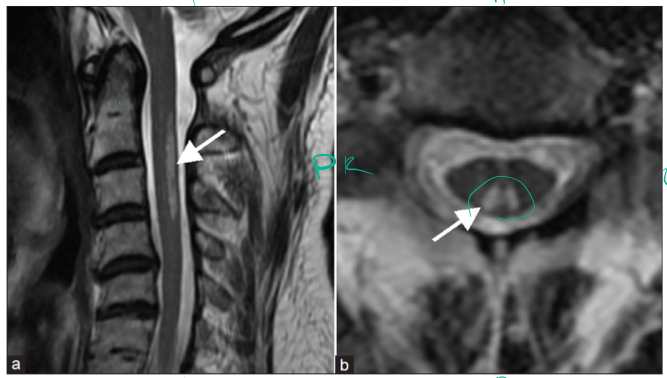

A 30 year old woman presents to the neurology clinic with numbness affecting both of her upper limbs and the upper half of her chest.

Sensory examination reveals she has bilateral loss of pinprick and temperatue sensation in the totality of her C4-T2 dermatomes.

Vibration, light touch and two-point discrimination are preserved.

Can you explain the bilateral nature of her symptoms and signs?

The lesion is found at the ventral white commissure where the spinothalamic system decussate.

Why are there no signs at levels below T2?

Because the lesion don’t extend that lateral and all axons inferiorly will pass laterally.

If the lesion continues to expand, how might her clinical picture change? Think about the location of the somatotopic organisation of the sensory tract.

Might go to lower limbs

Spinocerebellar tracts can be affected.

Motor functions might be affected.